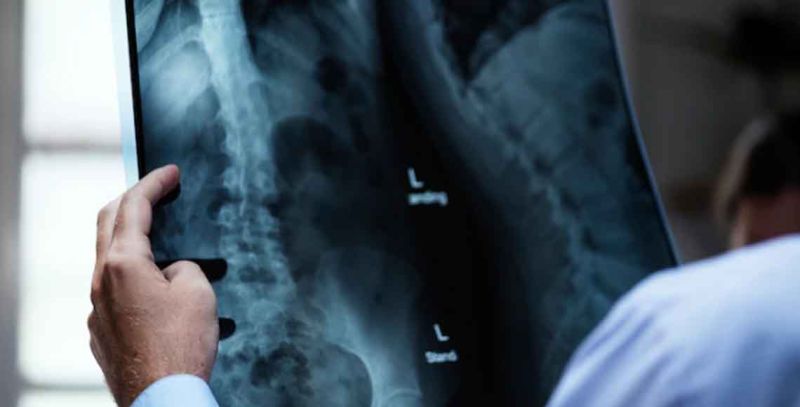

Rendgenski zraci koriste nevidljive snopove elektromagnetne energije da naprave slike unutrašnjih tkiva, kostiju i organa. Standardni rendgenski snimci se izvode iz više razloga, uključujći dijagnostikovanje tumora ili povreda kostiju. Rendgenski zraci prolaze kroz tkiva u telu praveći slike kostiju i organa.

Meka tkiva u telu (kao što su krv, koža, masnoća i mišići) omogućavaju da većina rendgenskih zraka prođe kroz njih i na snimku izgledaju tamno sivo. Kost ili tumor, koji je gušći od mekog tkiva, dozvoljava malom broju rendgenskih zraka da prođe i na rendgenskom snimku izgleda belo. Prilikom preloma kosti, rendgenski snop prolazi kroz slomljeno područje i pojavljuje se kao tamna linija u beloj kosti.

Rendgensko snimanje kičme se obavlja kako bi se procenilo bilo koje područje kičme (cervikalni, grudni, lumbalni ili sakralni) .

Rendgen torakalne kičme je pregled kojim se vrši snimanje bilo kakvih problema sa kostima u sredini leđa. Rendgen lumbosakralne kičme jeneinvazivna metoda snimanja, koja pomaže vašem lekaru da vidi anatomiju vašeg donjeg dela leđa.